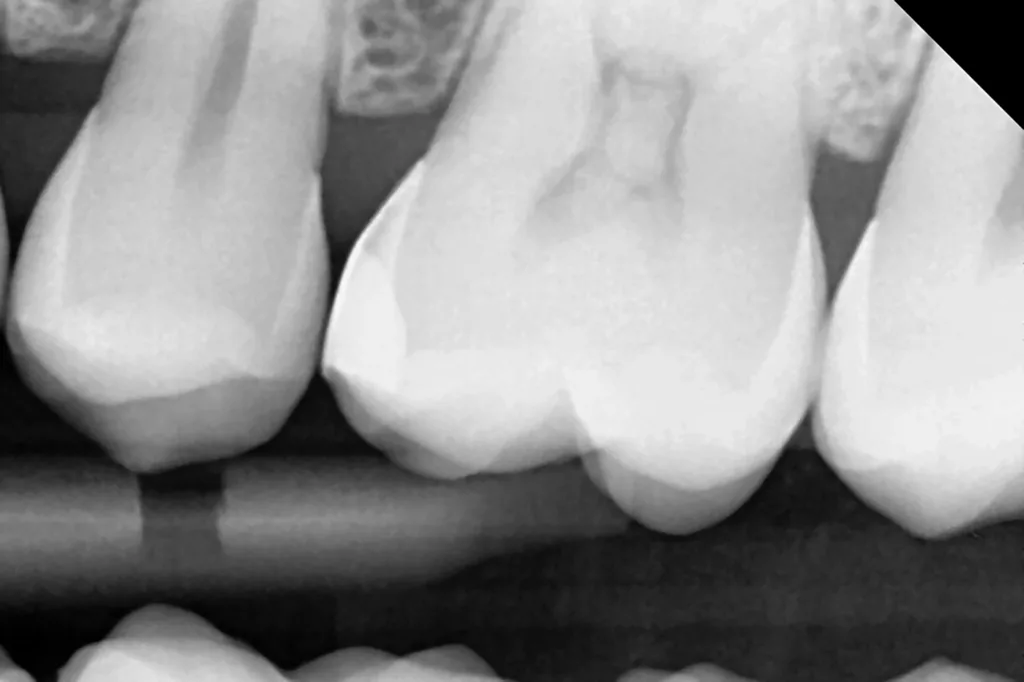

Die Abbildung 10 zeigt das Behandlungsergebnis unmittelbar nach Ausarbeitung und Politur (Diacomp Plus Twist, EVE), die Abbildung 11 bei einer weiteren Kontrolle nach sechs Monaten. In diesem Kontrolltermin wurden dann im routinemäßigen, zwei- bis dreijährigen Intervall Bissflügelröntgenaufnahmen zur Kariesdiagnostik angefertigt. Auf der Röntgenaufnahme zeigt sich die neue Visalys-Bulk-Flow-Restauration als randdicht, anatomisch korrekt geformt und ausreichend röntgenopak (Abb. 12). Die Schmelzläsion mesial an den Zähnen 15 und 16 erschien nicht therapiebedürftig, da die Oberfläche intakt war, wohl aber die versteckte Dentinläsion distal an dem Zahn 15. Der Defekt wurde in einem weiteren Termin identisch mit denselben Materialkombinationen und identischem Polymerisationsprotokoll versorgt (Abb. 13 bis 15).